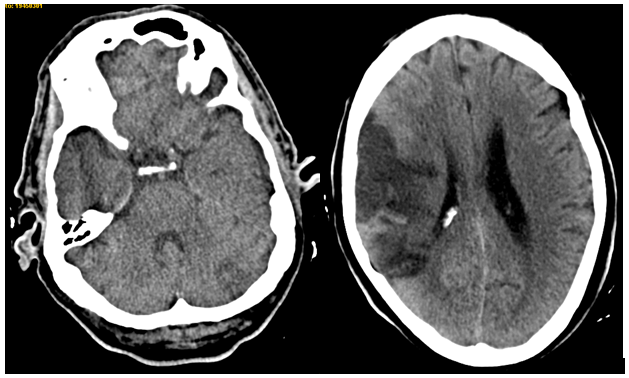

In the next hours, patient got progressively better so he only presented mild left hemiparesis and mild dysarthria. After 48hours, he presented again loss of consciousness followed by worsened dysarthria and nausea. Another CT scan was done, with a new hypodense lesion in left cerebellar hemisphere Figure 1. At that moment, neurological exam showed drowsiness, severe left hemiparesis, loss of sensitivity in left body, left Babinski sign, severe dysarthria and dysphagia.

Figure 1 Brain CT scan without contrast, showing right middle cerebral artery stroke and left cerebellar hypodense lesion.

Furthermore, a chest CT scan was performed, showing a lung lesion in the low left lobe including left bronchus, lung lymphadenopathy, left pleura metastatis, left kidney stroke and bilateral suprarenal metastasis. A brain MRI confirmed right middle cerebral artery stroke, left posterior- inferior cerebellar artery stroke and right anterior cerebral artery stroke (Figure 3).